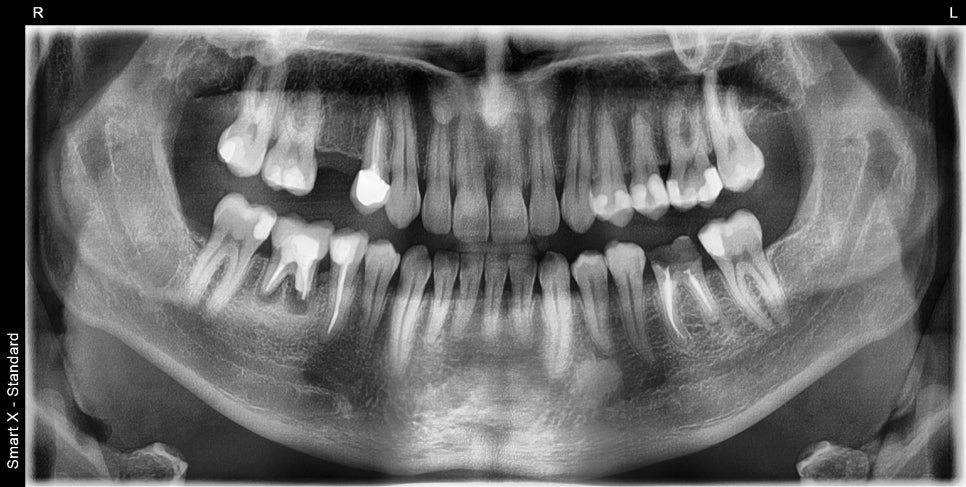

오래전 해외에서 치료 후 통증을 호소하며 내원하신 환자분 초진 파노라마 엑스레이 입니다.

오른쪽 아래 첫번째 큰 어금니는 뿌리끝 염증이 심했고, 좌측 첫번째 큰 어금니는 충치가 심해 머리부분 파절이 관찰되었습니다.

내원 당시 촬영한 위 아래 구강 내 사진입니다.

오른쪽 위 두번째 작은어금니의 상실로 임플란트 치료가 필요한 상태였습니다.